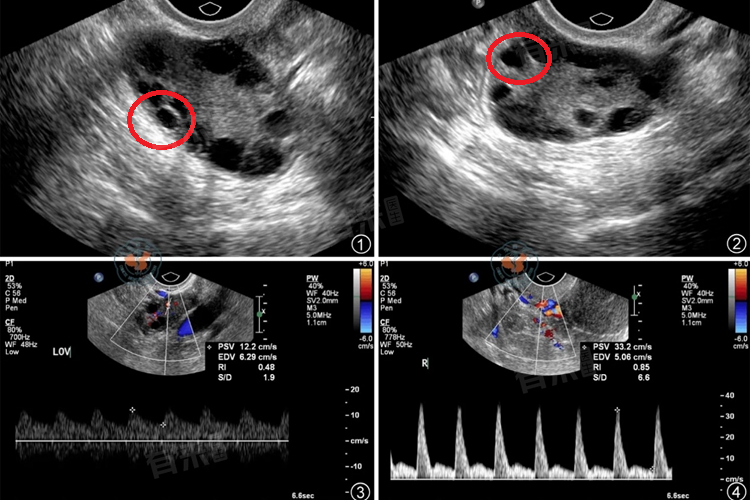

- 多囊卵巢综合征是另一种常见的子宫多囊类型,患者往往伴有月经不规律、排卵障碍等问题。由于激素水平异常,患者可能出现月经稀少、闭经等症状,导致不孕的风险增加。此外,多囊卵巢综合征患者即便成功受孕,也可能面临先兆流产、习惯性流产等风险。因此,这类患者在备孕前需接受全面检查,并在医生指导下进行治疗。

- 子宫多囊的病情严重程度直接影响怀孕的可能性。若患者病情较轻,囊肿较小且不影响生育功能,则怀孕的可能性较大。然而,若病情严重,囊肿较大且影响宫颈口通畅性或导致排卵异常,则怀孕难度增加。此时,患者需通过手术治疗或药物治疗等方式,先控制病情再考虑怀孕。